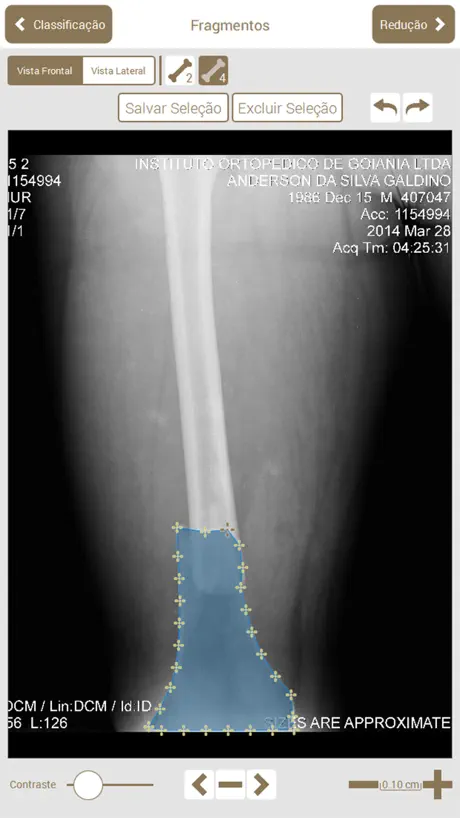

Osteotrauma é um aplicativo que auxilia no planejamento de cirurgias ortopédicas.

O objetivo do planejador é auxiliar o médico em todas as etapas do planejamento de cirurgias ortopédicas em fraturas de ossos longos.

No aplicativo, é possível executar os mesmos passos que são feitos em um planejamento manual: Escolha da radiografia, Classificação AO, Seleção e recorte das partes, Redução, Planejamento dos Implantes, Preenchimento da ficha do paciente, Geração de relatório e Edição manual do relatório gerado (que pode ser exportado em PDF).

O objetivo do planejador é auxiliar o médico em todas as etapas do planejamento de cirurgias ortopédicas em fraturas de ossos longos.

No aplicativo, é possível executar os mesmos passos que são feitos em um planejamento manual: Escolha da radiografia, Classificação AO, Seleção e recorte das partes, Redução, Planejamento dos Implantes, Preenchimento da ficha do paciente, Geração de relatório e Edição manual do relatório gerado (que pode ser exportado em PDF).